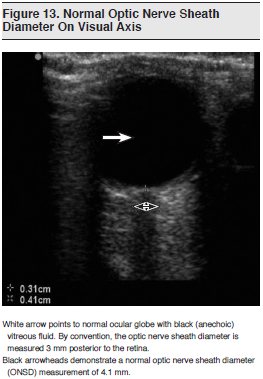

There is a growing body of literature describing the use of ocular ultrasound as a noninvasive method to detect elevated intracranial pressures (ICP). Increased ICP is transmitted through the subarachnoid space surrounding the optic nerve, causing expansion of the optic nerve sheath. The optic nerve sheath diameter (ONSD) can be measured on ultrasound using either the visual axis (probe placed directly over the closed eyelid in transverse orientation) or the coronal axis (probe placed temporally and directed nasally).108 (See Figure 13.) The approach most widely used is the visual axis, which measures the diameter of the optic nerve sheath at a point 3 mm posterior to the globe.109 Unlike most BUS examinations, which are adept at “ruling in” pathology, the current literature suggests that an ONSD of less than 5 mm may have excellent specificity for “ruling out” elevated ICP.

In an observational study involving 59 adult patients with head injury in the ED, Tayal et al measured ONSD using ultrasound and compared the results with CT findings suggestive of increased ICP.109 The finding of an ONSD greater than 5 mm on BUS had a sensitivity of 100% and a specificity of 63%, with a negative predictive value of 100% for the increased ICP noted on CT.

Using direct measurements of increased ICP by means of ventriculostomy (serving as the gold standard), 3 recent studies with slightly different protocols further characterized the direct correlation between ONSD and ICP with slightly varied results. The conclusion from these studies is that ONSD has a strong statistical correlation with ICP but that exact ICP prediction based on ONSD remains difficult and further studies evaluating different techniques are required. Ultrasound will not replace the need for invasive intracranial monitoring, but it can be used as a helpful bedside screening tool. A useful approach to assessing ICP is ONSD < 5 mm, no elevated ICP; ONSD > 6 mm, elevated ICP likely; ONSD = 5 to 6 mm, elevated ICP indeterminate/possible.